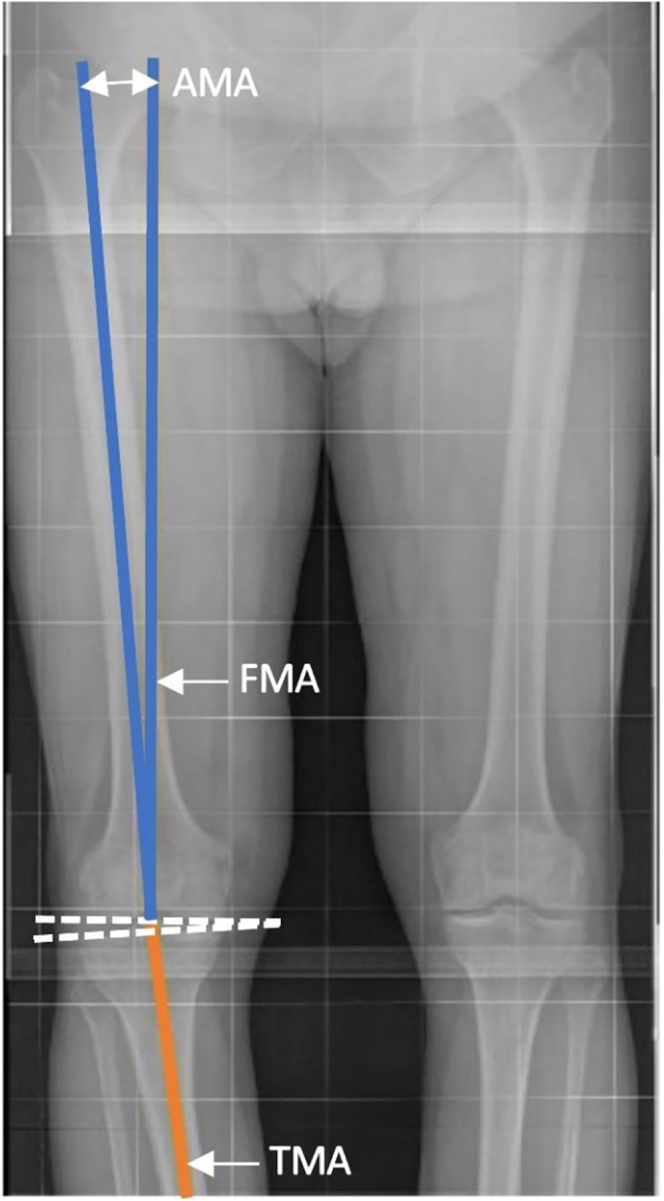

成功的全膝关节置换术的主要目标是减轻疼痛和恢复功能。虽然机械对准提供了良好的长期种植体存活,但临床和功能结果仍然不理想。因此,重点逐渐转移到基于患者具体特征的更个性化的手术方法。迫切需要在关键术语的定义上达成一致,以标准化肢体对准测量并改善该领域内的理解和交流。本研究的目的是澄清原生肢体对齐的概念,概述如何测量,并提出一个标准化的术语来描述它。

The main goal of a successful total knee arthroplasty is to relieve pain and restore function. While mechanical alignment provides excellent long-term implant survivorship, clinical and functional outcomes remain less than ideal. As a result, the focus has gradually shifted to a more personalized surgical approach based on the patient's specific characteristics. There is a pressing need for agreement on definitions of key terms to standardize limb alignment measurements and improve understanding and communication within the field. This work aims to clarify the concept of native limb alignment, outline how it is measured, and propose a standardized terminology to describe it.